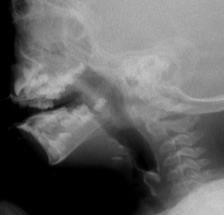

Videofluoroscopy

ORAL PREPARATORY PHASE IN EATING SOLID FOOD

✓ Loss of food out mouth, pushed out with tounge

✓ Food in anterior sulcus

✓ Limited tongue movement

✓ Problem about turning the food into bolus formation

✓ Food in valleculae and pharynx,

pre swallow

✓ Jaw grading inappropriate

ORAL PREPARATORY PHASE IN DRINKING LIQUID FOOD

✓ Loss of food out mouth

✓ Liquid in anterior sulcus

✓ Food pushed out with tounge

✓ Food in valleculae and pharynx, pre swallow

ORAL PROPULSIVE. PHASE:

✓ Food or liquid remains in anterior and/or lateral sulcus

✓ Food or liquid remains on floor of mouth

✓ Limited posterior tongue movement

✓ Reduced base of tongue action

✓ Tongue-soft palate contact incomplete

✓ Multiple swallows per bolus

✓ Delayed oral transit time

PHARYNGEAL PHASE

✓ Nasopharyngeal regurgitation

✓ Slow bolus passage through Pharynx

✓ Reduced pharyngeal contraction/motility

✓ Residue cleared with next swallow

✓ Residue not cleared

✓ Reduced hyolaryngeal execursion

✓ Penetration to underside of epiglottis

✓ Penetration to laryngeal vestibule

✓ Aspiration before, during and after swallow

✓ Aspiration respons: not effective cough, no cough – silent aspiration

ESOPHAGEAL PHASE

✓ Slow bolus passage through UES

✓ Residual on UES

✓ Cricopharyngeal dysfunction

✓ Slow bolus passage through esophagus